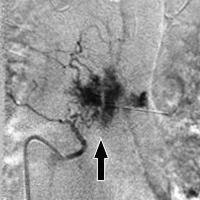

Principalele metode moderne de diagnostic - computer si imagistica prin rezonanta magnetica, de examinare cu raze X a coloanei vertebrale, precum și formarea de angiografie anormale cu injecție de contrast și producerea unei serii de imagini. Mai mult decât atât detectarea și diagnosticarea hemangiom, metode suplimentare de examinare efectuate în scopul de a monitoriza și controla un neoformație benigne. Urmărirea rata de creștere și luând în considerare cele mai structura tumorii pathomorphology, datorită observației dinamice a rezolvat problema modului de a trata hemangioame a coloanei vertebrale.

Ca introducere varietate scleroterapia utilizată de agent de spumare care este livrat printr-un cateter direct in tumora. Acesta acționează ca un embol, nave de aprovizionare și sigilarea livrarea de oprire a nutrienților în vatra creșterii patologice, determinând treptat să regreseze și scleroză. Această metodă este folosită atunci când nu există nici un pericol de o fractură de compresie a corpului vertebrale, precum și probabilitatea de sângerare nave gemangiomatoznyh.